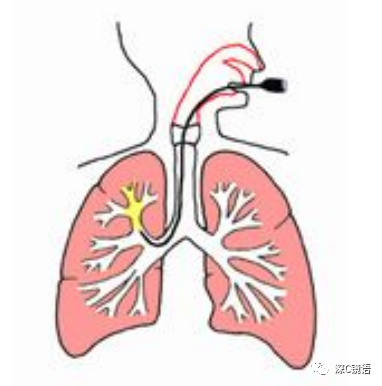

支气管镜是一根直径为4到6毫米的细而柔软的管。它是一种仪器,既可观察支气管,又可观察与支气管连接的胸腔深部的肺脏。它具有与胃镜相同的结构,但比胃镜细小得多。

为了准确诊断肺部和支气管等呼吸系统疾病,将支气管镜通过口或鼻腔,经咽喉部插入气管和支气管,观察管腔和组织并收集样本(例如分泌物和细胞)的一种检查。在气管分支为左支气管和右支气管之后,每个分支进一步重复分支,直至到达控制呼吸的肺泡。支气管的每次分支都会变细,使用支气管镜可以观察支气管的内腔,通常将其称之为段支气管,直径约为5毫末。如果您有以下症状或发现,我们建议进行支气管镜检查: 3.当胸部X线或CT扫描显示肺部异常阴影,并且怀疑肿瘤或结核时 3.检查过程中,您需要吸氧,并连接监测仪器进行心电和血脉氧监测。4.当您平卧在床上后,支气管镜将从口腔或鼻腔进入,经过喉咙进入气管支气管。如果是从口腔入镜,则需要将咬口器放到嘴里。如果是从鼻腔入镜,则对鼻腔进行局部麻醉。 5.通过观察支气管来确认病变是否存在。如果过程中出现咳嗽,则在支气管内再次进行局部麻醉。在检查过程中,你可以正常呼吸,但由于支气管镜穿过声门所以无法发出声音。如果您有任何异常不适,请及时向医生发出信号(例如使用手势)告知我们。检查期间,放松肩膀并轻柔呼吸。切勿触摸支气管镜或其他仪器,因为这存在危险。 6.另外,为了明确诊断,可能需要从适当的区域收集细胞和组织。 7.确保没有出血等并发症,可移除支气管镜并结束检查。检查时间通常为20至30分钟,根据检查和治疗内容的不同,所需的时间也有不同。8.咽喉部麻醉效果不会立即消失,检查后2小时内请勿喝水和进食。根据检查的内容,可能会出现以下并发症,如有出现并发症可能需要进一步的手术和医疗措施。1.肺和支气管出血(发生率0.66%):当收集细胞和组织学样本时,总是伴有少量出血。通常少量出血能自行止血,但在极少数情况下,出血无法自行停止,需根据情况采取干预措施。包括注射止血药物或插入封堵器以阻塞出血的支气管。更严重的情况可能需要紧急气管插管。 2.气胸(发生率0.4%):组织活检时,肺部的脏层胸膜可能会受损,如果空气从受损处泄漏,则可能导致“气胸”并压迫肺脏。这种情况的气胸通常较为缓和,只需要休息几天。当合并肺气肿等基础病变时,气胸可能会持续漏气,因此而需要进行胸腔闭式引流术。 3.发热和肺炎(发生率0.22%):检查后很少发生,即使发生大多数也是暂时性的,根据情况可能需要使用抗生素。 4.麻醉药引起的过敏或中毒(发生率0.04%):在极少数情况下,局部麻醉药利多卡因可能会发生过敏反应。出现时需立即停止支气管镜检查并进行相应处理。过量的麻醉药物可能引起中毒症状(焦虑,兴奋,头晕,血压下降,心律不齐,抽搐等)。这些症状一般会随着时间流逝和药物的代谢而消失。 5.其他:比较罕见如哮喘(发生率0.07%),呼吸衰竭(发生率0.09%),心肌梗塞心律不齐等其他心血管疾病(发生率0.07%),支气管阻塞(发生率0.02%),以及非常罕见的意外事故导致的死亡(发生率0.004%)。很遗憾的是,目前无法通过CT,MRI,PET等影像手段来获得肺部病变的明确诊断。可替代支气管镜的方法包括以下内容。 1.CT引导的肺活检:主要针对肺部病变。在CT确认病变确切位置的同时,在局部麻醉下,将一根细针刺入胸部以从病变中收集样本。这种方式的气胸等风险增加,住院时间可能更长。 2.手术活检:包括胸腔镜活检和开胸活检。两者均需要在全身麻醉下进行。胸腔镜活检通常需要在胸部皮肤上做1-3个切口,胸腔镜插入胸腔后观察的同时切除病灶并收集样本。开胸活检需要打开胸腔进行观察和病灶切除。两种方法的诊断率都很高。 3.纵隔镜活检:主要用于纵隔肿大淋巴结或纵隔肿块的活检。需要在全身麻醉下进行,从胸骨上方的皮肤切口插入纵隔镜,观察纵隔内部并收集样本。并发症包括出血和声音嘶哑等。以下(常见但不限于)方法可经支气管镜对支气管和肺疾病进行治疗。 1.热消融术(高频电,微波,激光,氩等离子体凝固)